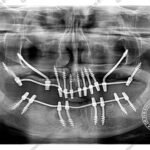

1005 zygomatic basal implant full mouth Ali Hasan 2

C1005 zygomatic basal implant full mouth – Ali Hasan 4